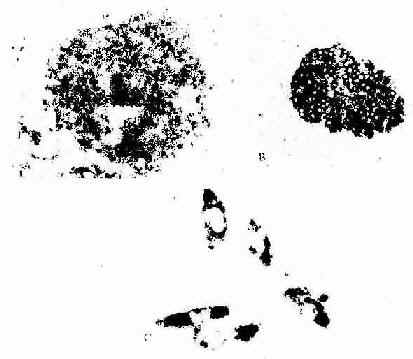

大鼠肝大部切除后再生过程中增殖期肝细胞

图1-11 大鼠肝大部切除后再生过程中增殖期肝细胞

摄取3H标记的胸腺嘧啶核苷放射自显影

↑ 增殖期肝细胞核